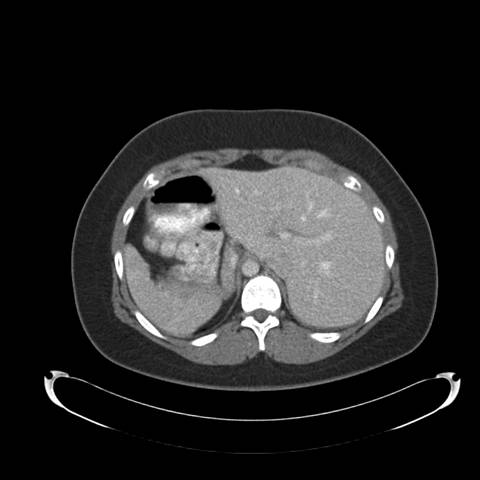

Figure 2: High resolution computed tomography (CT) of the Chest —demonstrates situs inversus totalis and volume loss of the "left middle lobe" with bronchiectasis, presumably fibrotic.